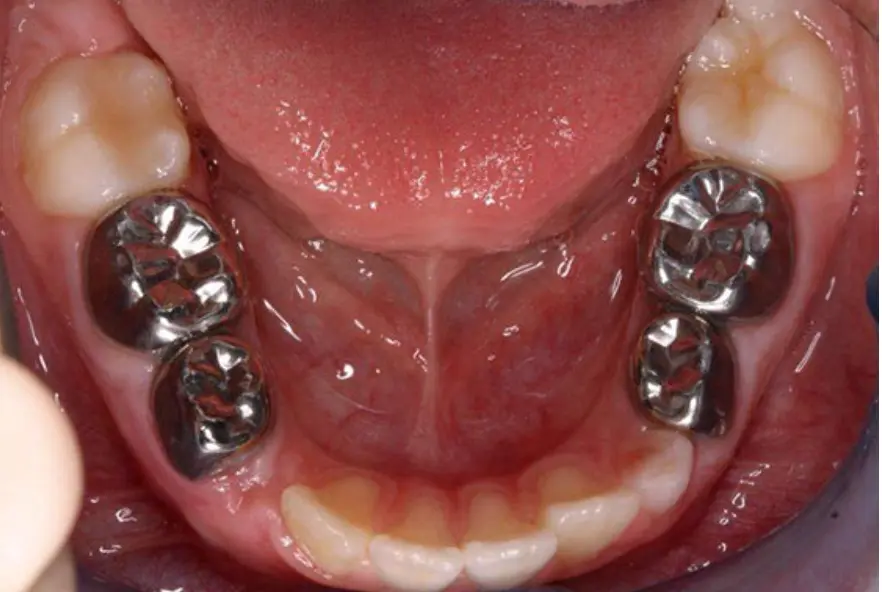

Детские зубные коронки

Значительное разрушение зубов у детей давно не приговор – восстановление возможно при помощи коронок. Часто этот способ лечения ассоциируется со взрослой стоматологией, но на самом деле детские зубные коронки появились в 50-х годах прошлого века и сейчас активно используются в зарубежной практике.